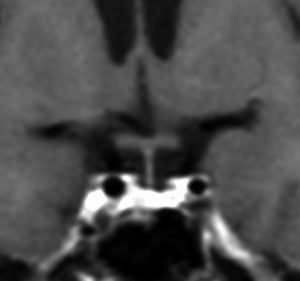

この例は古いので第3脳室開窓術 ETV をしていません。左はICE化学療法前。中央は9日後。右は25日後です。閉塞性水頭症があっても1週間くらいで中脳水道が通って水頭症は改善します。ジャーミノーマであれば,ICE化学療法1コースでかなり縮小するはずです。このような顕著な効果がない時には,逆にジャーミノーマ以外の胚細胞腫瘍が混在していると考えた方がいいでしょう。多くは奇形腫の混在です。